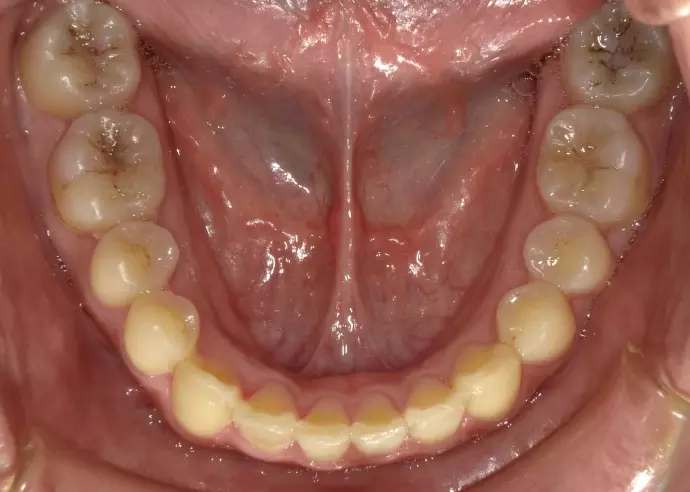

過蓋咬合といいますが、下の前歯が隠れてしまうような深い咬み合わせでした(黄色の矢印部)。また右下の前歯は重なりがひどい状態でした。通常は下の中間の歯を抜歯して治療されますが、矯正用のインプラントを利用して歯を抜歯しないで治療が終了したケースです。

前歯の咬み合わせについては下の前歯が隠れてしまうような深い咬み合わせでした(過蓋咬合)。また右下の前歯は重なりがひどい状態でした(黄色の矢印)。

治療前は凸凹がひどく、中間の歯を1本抜歯して治療する可能性がありましたが、矯正用のインプラントを使う事により、抜歯の必要がなくなり治療を終了することができました。前歯の深いかみ合わせ(過蓋咬合)も治っています。